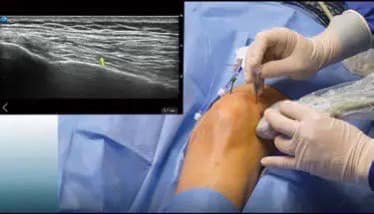

Coolief疼痛管理用高周波システム

痛みを感じる神経に高周波電流を流し、神経を部分的に焼灼することで痛みを落ち着かせる方法です。